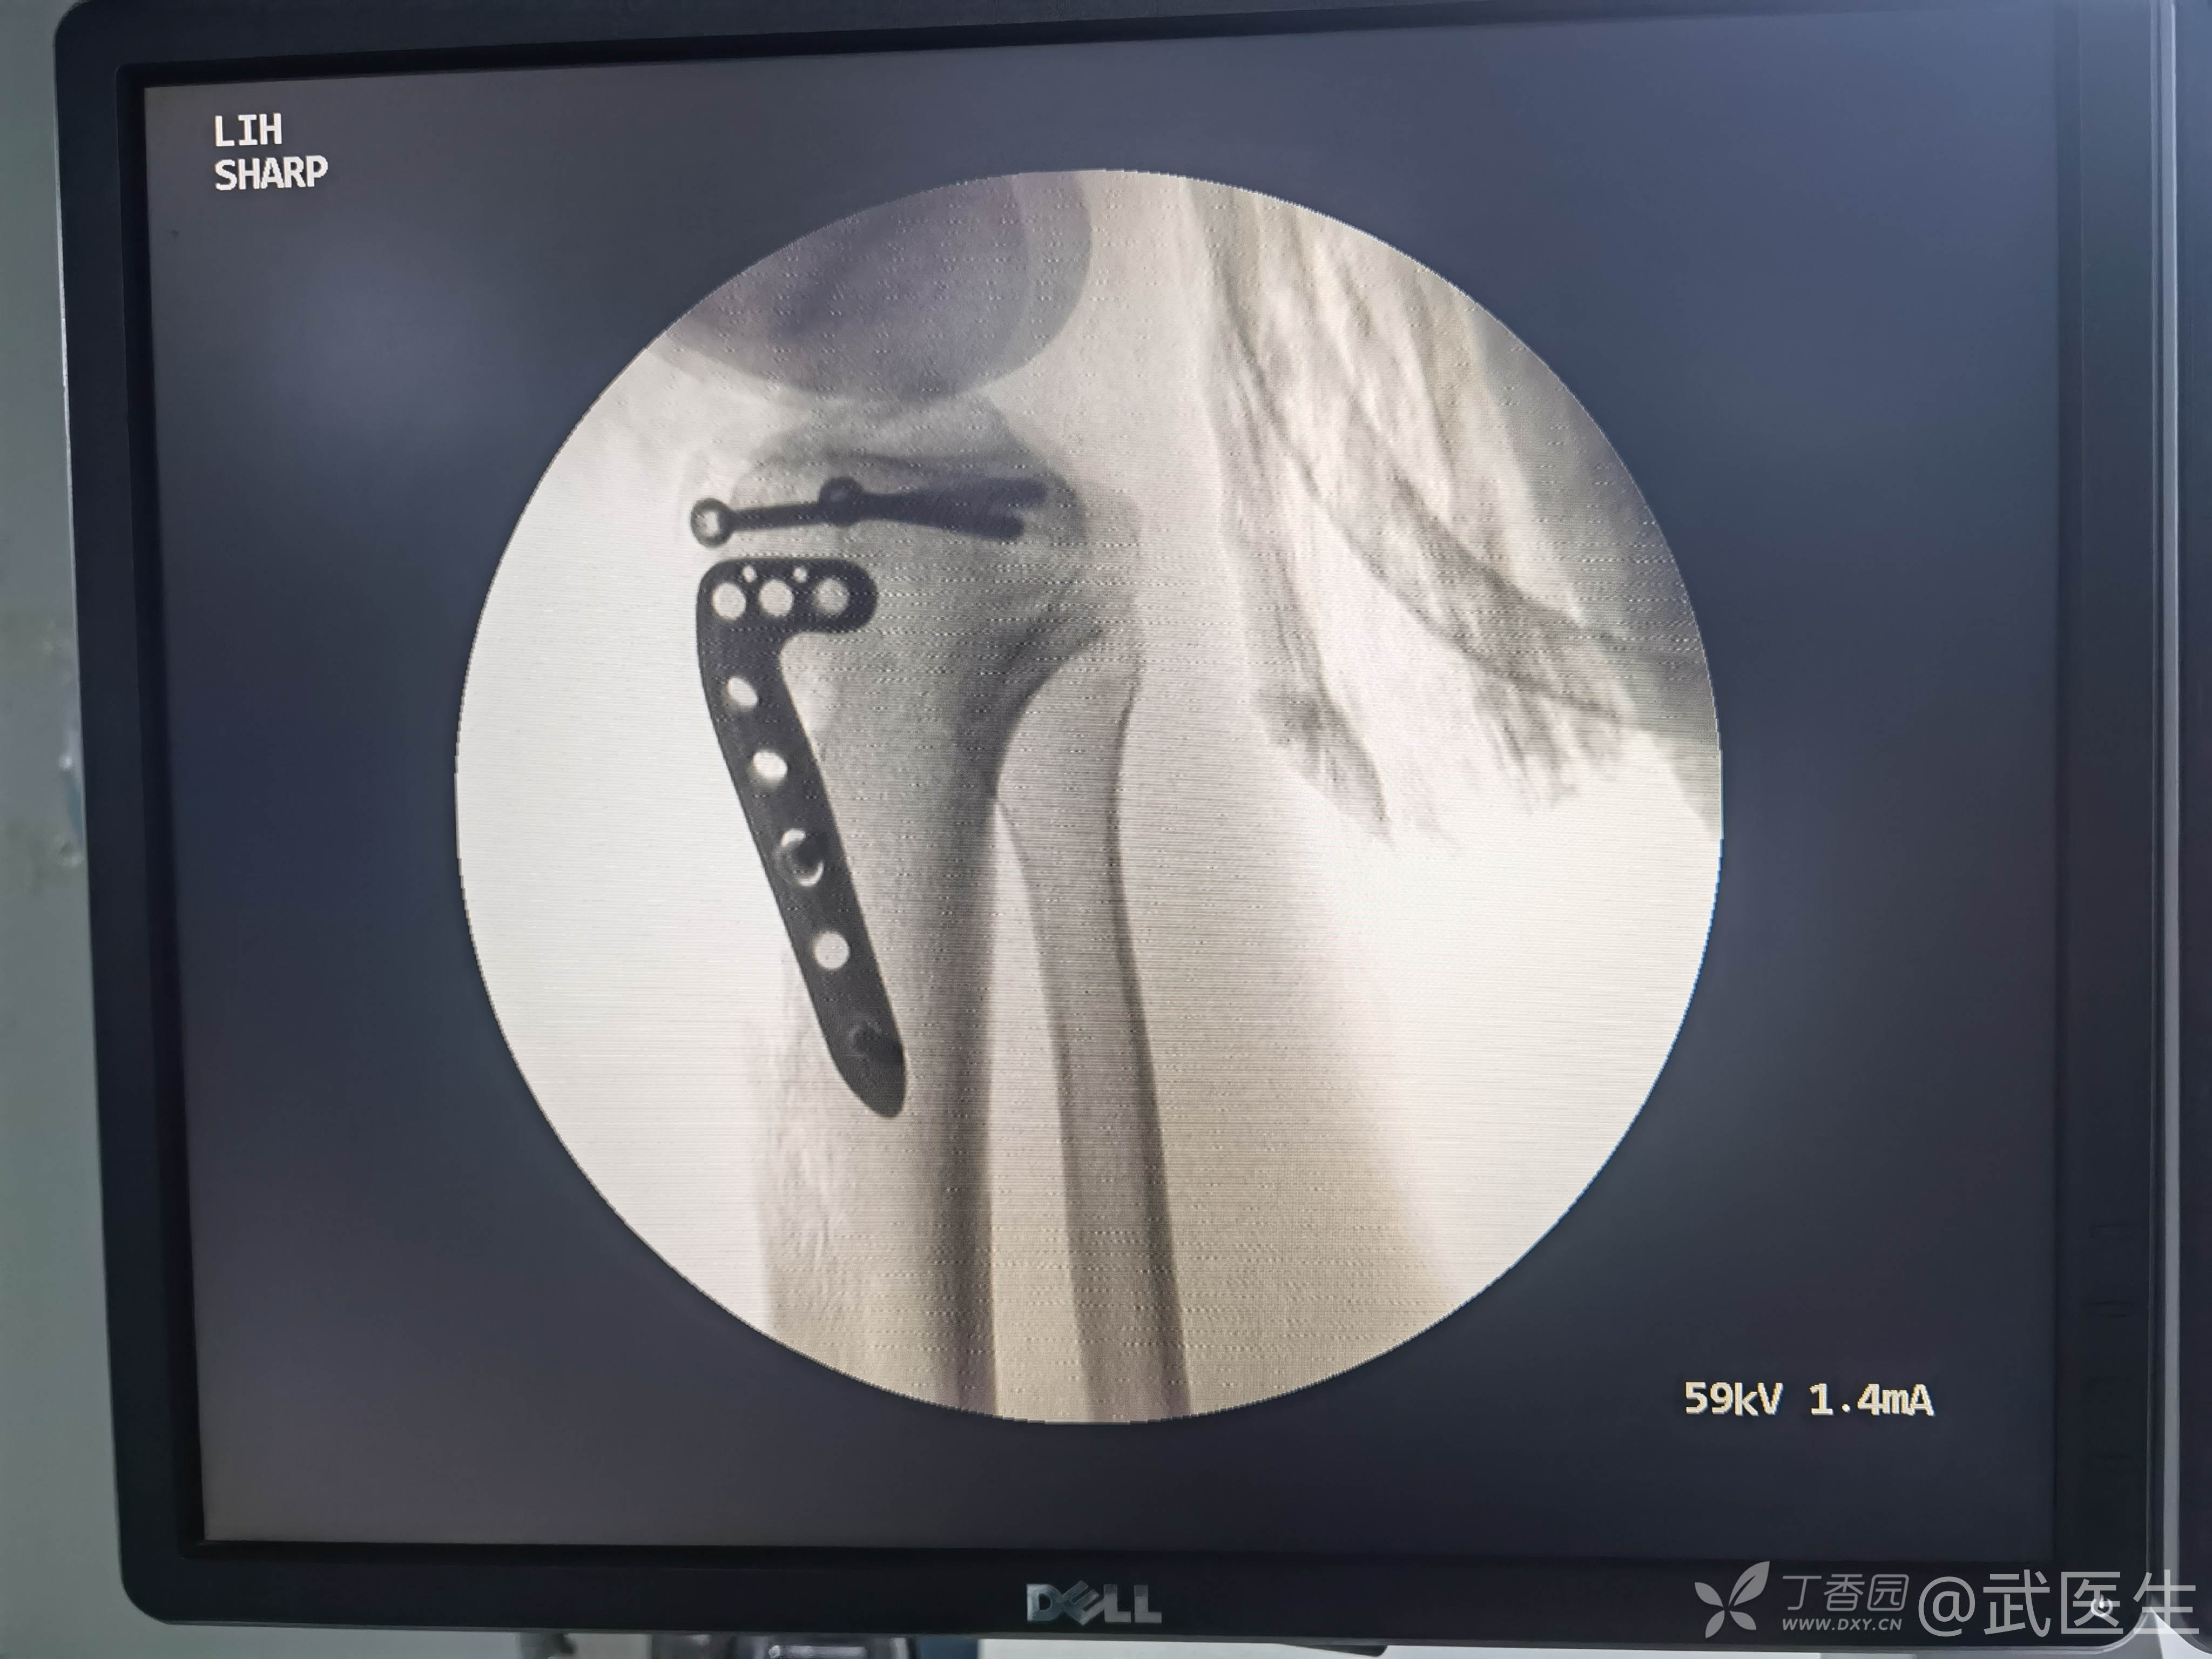

15岁,骨骺存在,关节加压固定,外侧板支撑